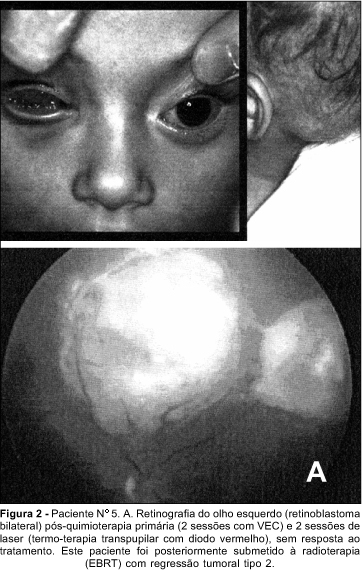

5 - Os pacientes foram distribuídos de acordo com a presença ou não de doença extra-ocular no momento do diagnóstico: GrupoI- Cinco pacientes receberam quimioterapia como tratamento primário, 4 obtiveram redução tumoral sendo que 2 responderam apenas inicialmente indo a óbito em 10 meses de média. O número de ciclos de quimioterapia usado foi em média de 3 (variando de 2 a 5 ciclos). O tempo médio de seguimento após quimioterapia primária foi de 12,4 meses (variação 6-18 meses) até o presente momento. Dois pacientes desenvolveram metástase após início da quimioterapia primária. Quatro pacientes foram submetidos à enucleação do pior olho, ou olho preenchido por tumor. Um paciente (Fig.2, caso nº 5) apresentou sementes vítreas durante o tratamento com quimio e laser (termo-terapia), como já havia sido enucleado o olho pior (grupoV), necessitou tratamento complementar com radioterapia (EBRT). Atualmente, 4 meses pós EBRT, apresenta regressão tipo 2 das lesões intra-oculares e visão 20/25. Outro paciente (caso nº 4) tratado com radioterapia (EBRT) no olho menos acometido, foi submetido a enucleação do segundo olho devido a descolamento da retina em funil com fibrose e calcificação após a radioterapia. O anatomo-patológico revelou que mesmo o segundo olho enucleado continha células tumorais viáveis (Fig. 3.A) e invasão do corpo ciliar (Fig. 3.B). GrupoII- Dois pacientes submetidos a enucleação primária com quimioterapia adjuvante, média de 3 ciclos (variando de 2 a 5 ciclos). Estes já apresentavam metástase cerebral e foram a óbito em média aos 4,5 meses de seguimento. Esse grupo foi submetido a enucleação imediatamente após diagnóstico por serem casos avançados com comprometimento extra-ocular e grande volume tumoral. A intervenção cirúrgica teve como objetivo diminuir a massa tumoral a ser tratada.